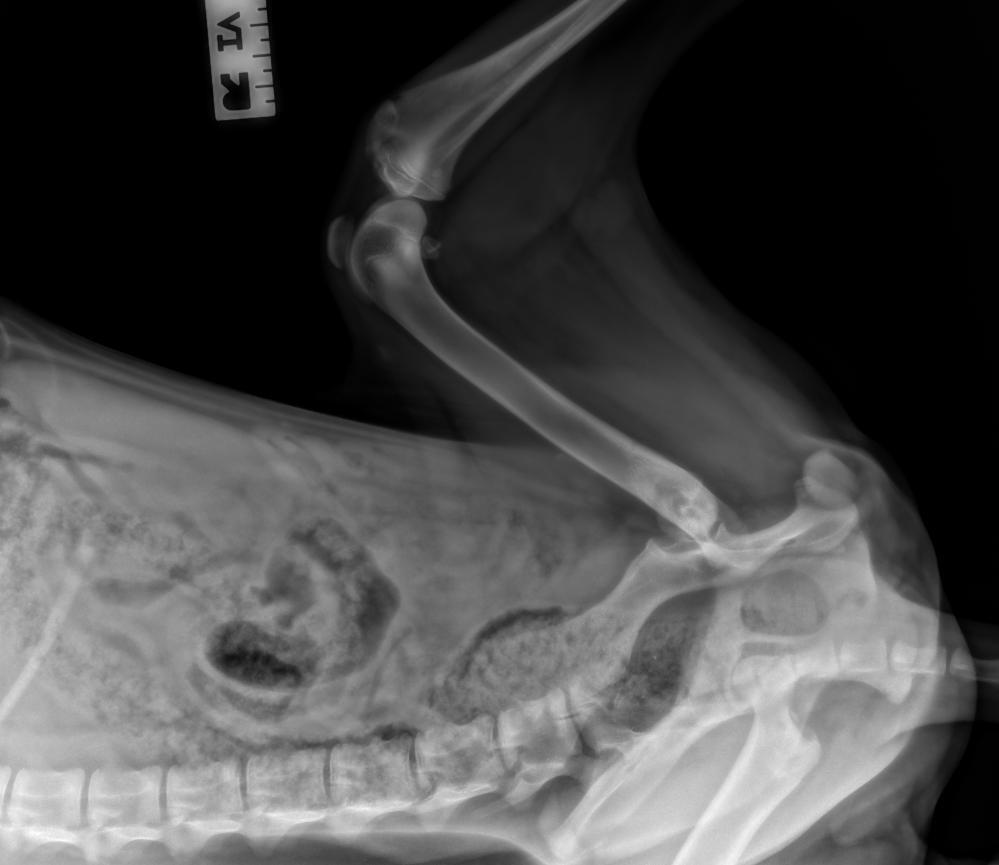

Just a baby, at 6 months old, Cocoa had lived more than 1/3 of her life on a cold shelter floor. You might call her lucky, to make a life saving trip and to land in a warm and loving foster home- but upon arrival, it was quickly discovered that something was terribly wrong. Cocoa's back leg bone, where it fits into her hip (femoral head) is not where it's supposed to be, and it's broken. She's been suffering with this debilitating pain, for no less than 2-1/2 months, likely longer. So maybe she IS lucky- we sure hope so- because with any luck, you will donate to help us raise enough money to cover the cost to have her painful, broken, baby leg- fixed! (more photos below)